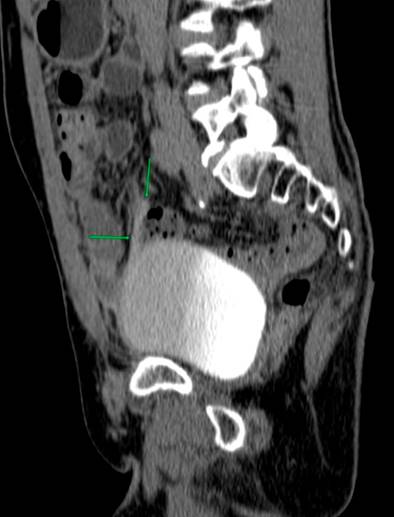

Due to the recurrence of the symptoms, chronicity, absence of etiology after a detailed study, and taking into account the patient’s surgical history, less frequent etiologies were considered a possibility of uroperitoneum. Creatinine was measured in the peritoneal fluid, the result of which was 7.44 mg/dL, and the gradient between fluid and serum was 5.74, which further increased the suspicion. Due to the uncertainty in the face of acute kidney injury and suspicion of urinary fistula, the nephrology service requested a voiding cystography with dynamic films, finding a bladder dome defect with active contrast extravasation into the peritoneal cavity, which confirmed the presence of uroperitoneum and explained the elevation of nitrogenous gases that simulated acute renal injury (Figure 1). To better characterize the genitourinary tract lesion and surgical planning, a urotomography was performed (Figure 2) with evidence of a defect in the bladder dome of 7.8 mm towards the right side in its anterior portion, with evidence of extraluminization of the contrast medium as a sign of rupture. After this characterization, he was scheduled for laparotomy with cystorrhaphy, performed at another institution.

Voiding cystography is the gold standard for diagnosing bladder rupture, with a sensitivity and specificity of 95% and 100%, respectively33. However, with the availability of new techniques, CT cystography has a performance comparable to voiding cystography, especially if injuries to other organs must be ruled out, which is common in traumatic bladder ruptures in multiple trauma patients33,34.